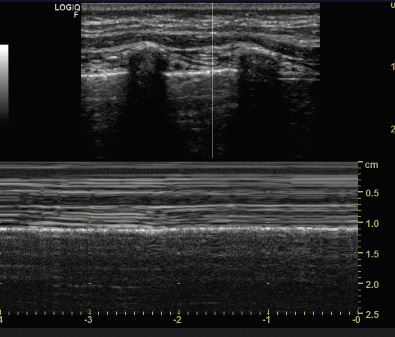

• En modo M: este movimiento genera la imagen de la “orilla del mar” (“seashore sign”), donde la zona superior (pared torácica inmóvil) presenta un patrón de líneas paralelas horizontales “olas”, y la inferior (pulmón ventilado/móvil) un aspecto granular “arena”, que confirma la presencia de aireación normal (Fig. 6).

Figura 6. Imagen de la orilla del mar.